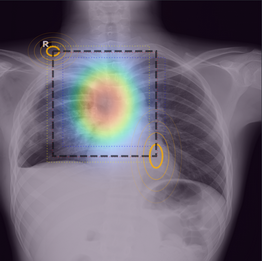

Der übliche Ansatz besteht darin, aus diesen widersprüchlichen Labels eine einzige Ground Truth zu aggregieren. In diesem Projekt verfolgen wir einen anderen Ansatz: Wir betrachten diese Meinungsverschiedenheiten als wertvolles Supervisionssignal, das inhärente Variationen erfasst. Im Laufe des Projekts werden wir neuronale Netzwerkdesigns untersuchen, die in der Lage sind, direkt aus Meinungsverschiedenheiten zu lernen. Zudem werdenb wir Bewertungs- und Diagnosetools für diese Aufgabe anpassen und unsere Methoden an einer Auswahl von Datensätzen aus verschiedenen Bereichen testen.